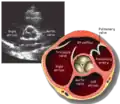

This view is obtained in the same window as the parasternal long, but with the probe rotated 90°. In this view, the aortic valve is seen in cross-section with the right ventricular inflow & outflow tracts visible with the tricuspid valve as well. Pulmonary valve is not visible in this view. Both the right and left atria are visible.

- Aortic valve in short-axis

- Aortic valve dysfunction, aortic sclerosis/stenosis

- Aortic valve area by planimetry

- Color doppler of all four valves

- Spectral doppler of tricuspid and pulmonary valves